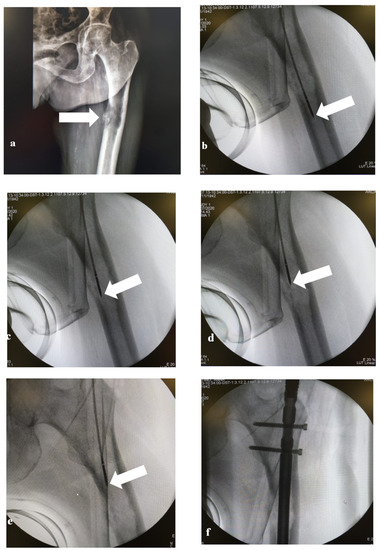

2. Materials and Methods

2.2. MWA Technique

2.3. Surgical Technique